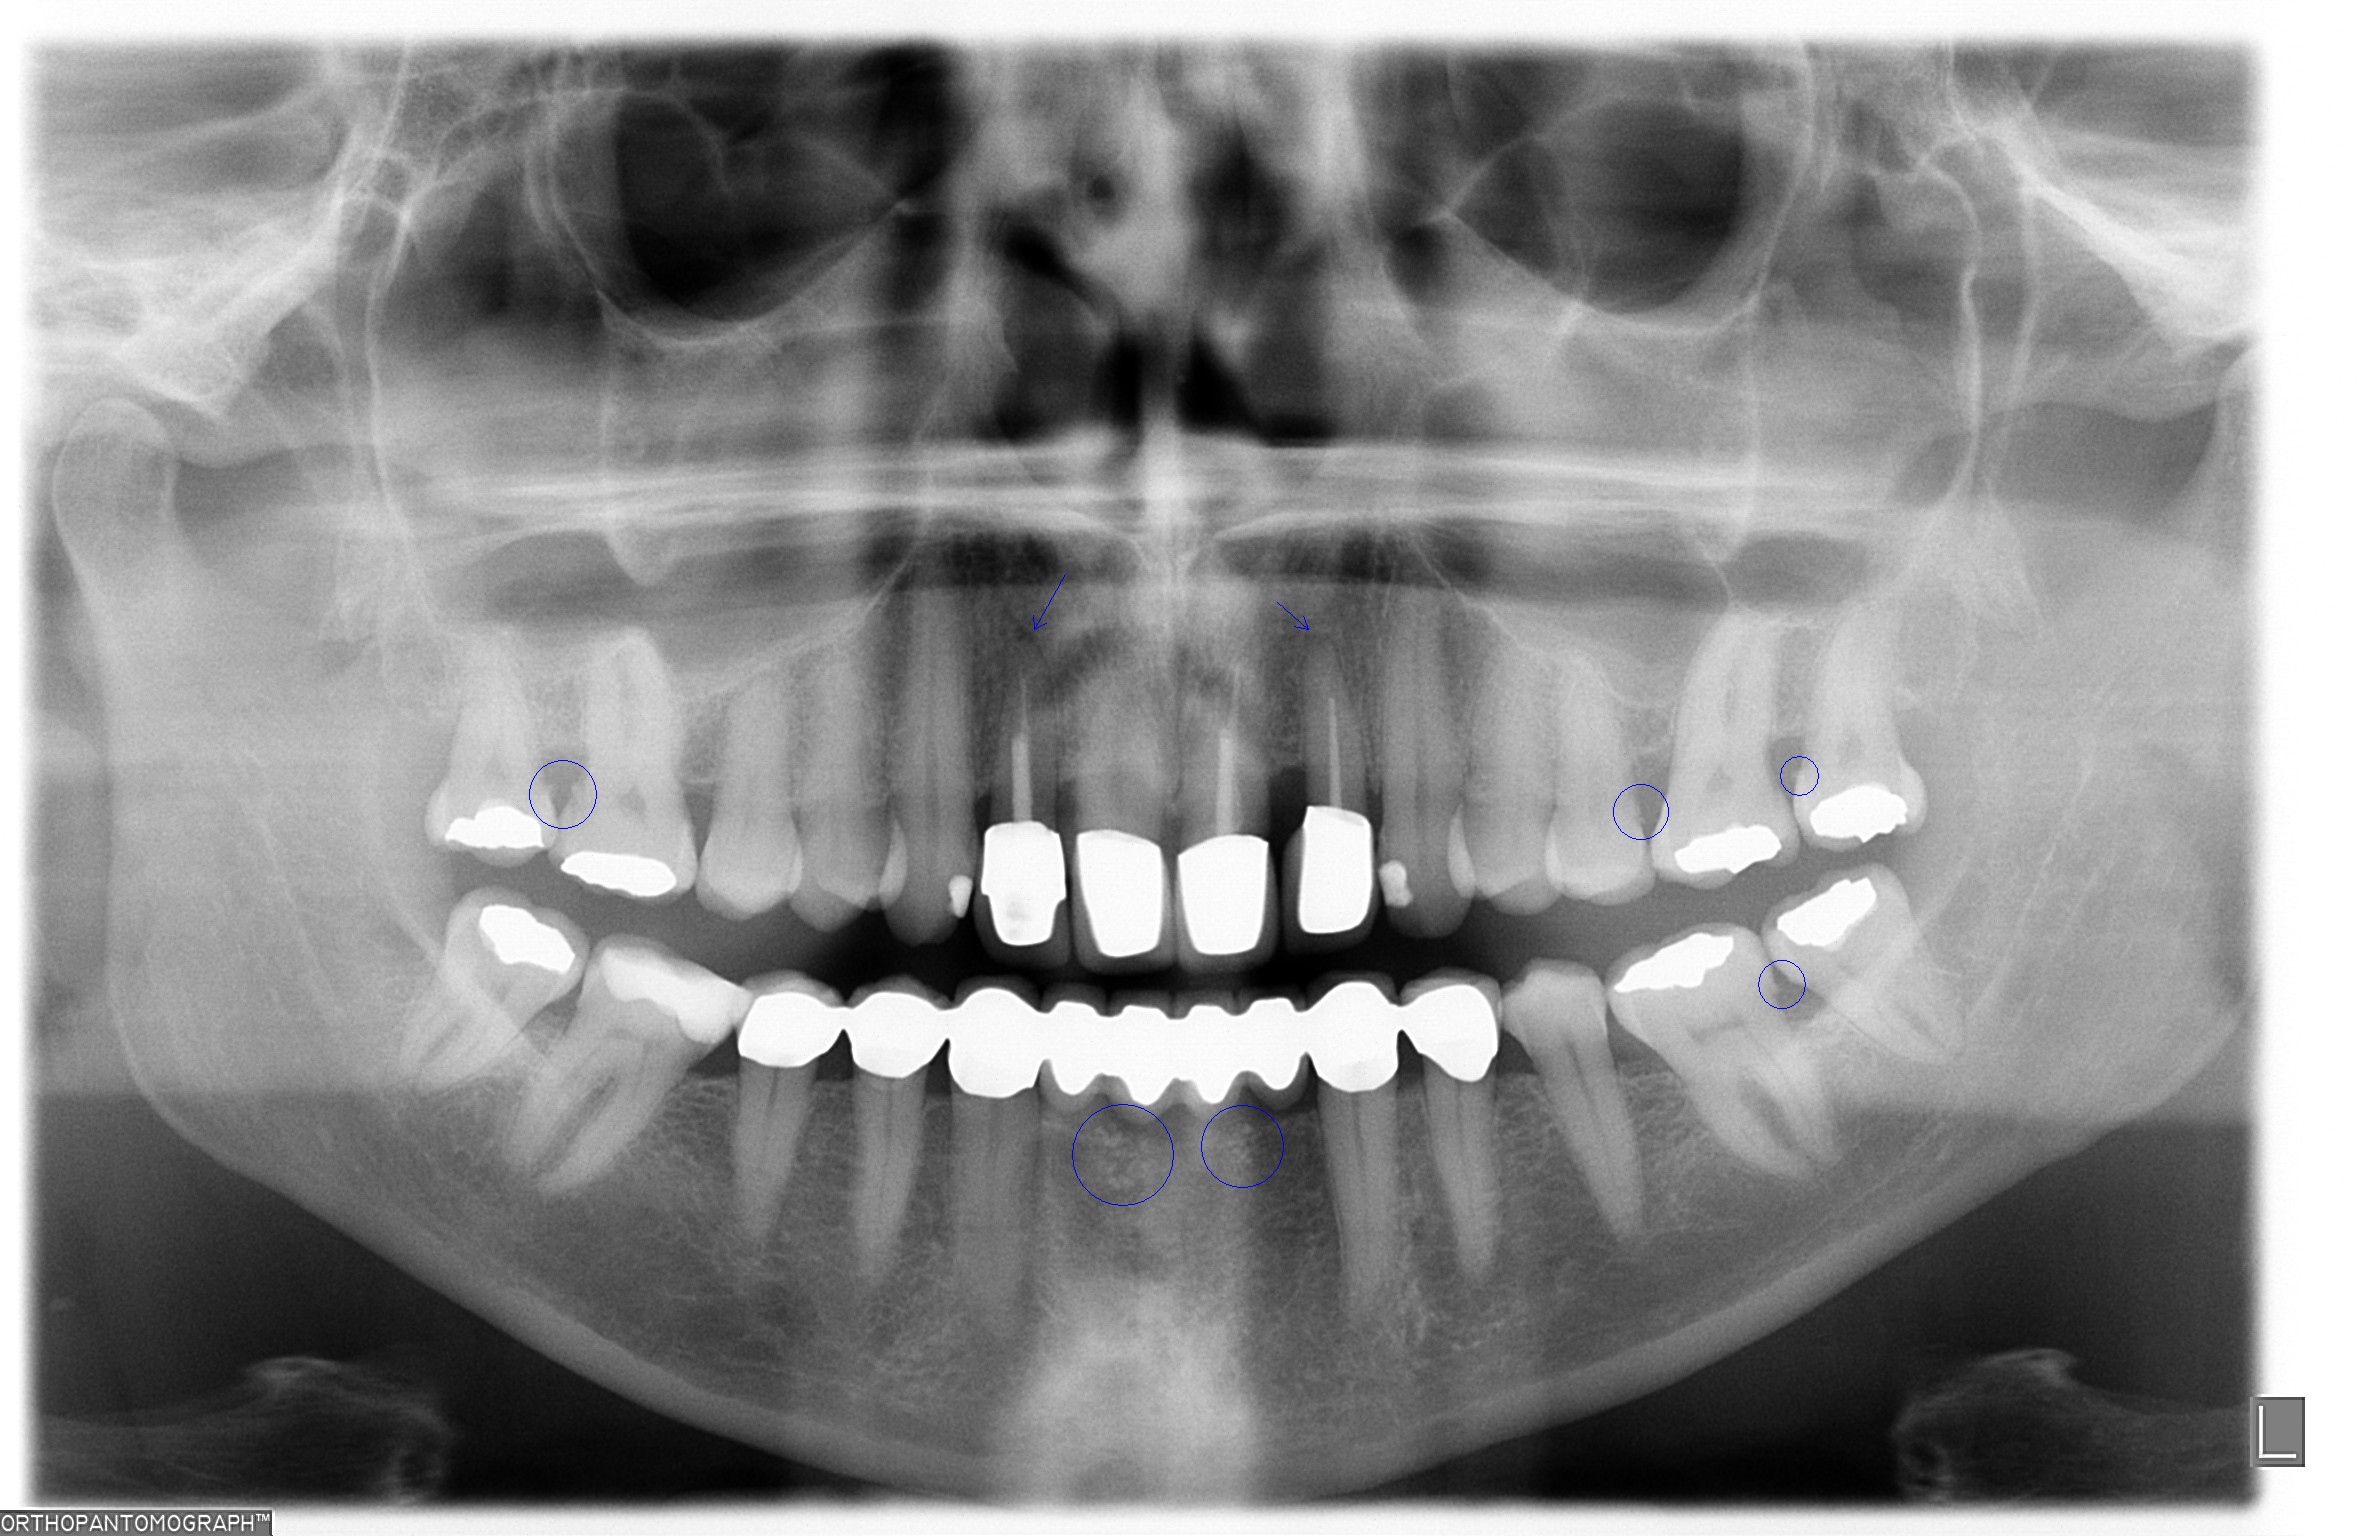

I. Befund des gesamten Gebisses / Behandlungsplan

Oberkiefer

11 KM kw kw KM 21

12 KM kw kw KM 22

13 PKM pw pw PKM 23

14 24

15 25

16 F2 c c F2 26

17 c F2 27

18 f f 28

Unterkiefer

48 f f 38

47 F2 c c F2 37

46 KM ww c F2 36

45 KM kw 35

44 KM kw kw KM 34

43 KM kw kw KM 33

42 SKM b b SKM 32

41 BM b b BM 31

• Sedierung: 2x Lachgas inkl.

• mit Freilegung

• mit Auswechseln der Sekundärteile

• Knochenaufbau: 1x Regio 32-42

• Funktionsanalyse

• dent. Aufbau: 9x Zahn 12-21, 33, 34, 43-46

• Glasfaserstift: 1x Zahn 22

• Langzeitprovisorium: Zahne 22, 32-42

• inkl. Knirscherschiene OK

• 2x inkl. Professionelle Zahnreinigung

• Wurzelrevision Zahn 22

• PRF-Verfahren

• Füllungstherapie Zähne: 16, 26, 27, 36, 37, 47